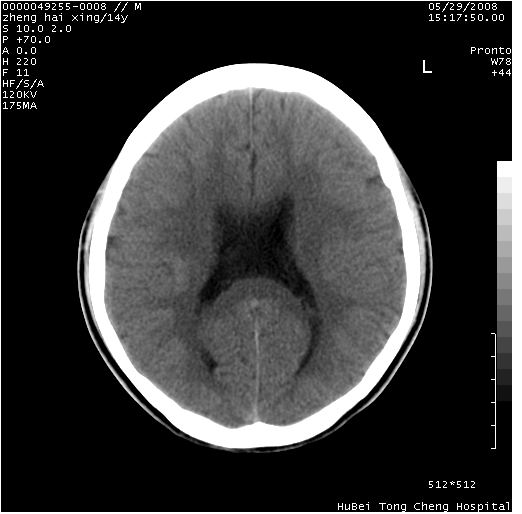

颅脑ct轴位平扫(层厚、层距均为10mm),图像如下:

双侧侧脑室之间无透明隔,双侧额角前方变扁,交角变钝。支持透明隔缺如!

调一下窗寛窗位,或者透明隔太薄,容积效应而显示不好。